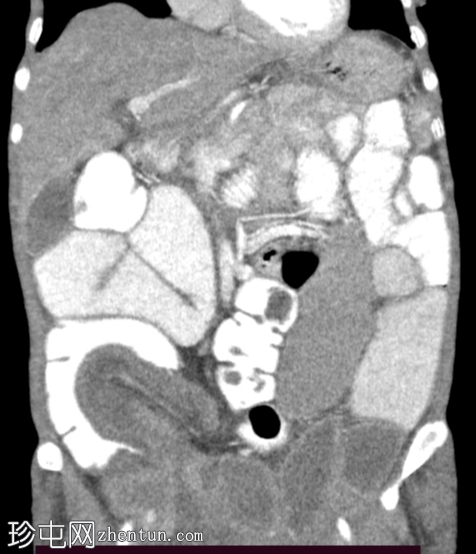

冠状位增强扫描

动脉期

回肠肠袢套入盲肠,形成肠套叠形态,轴位和纵位图像分别可见靶征和腊肠征或假肾征。

病例讨论

成人回盲部肠套叠较为罕见。然而,它是由潜在的“引导点”引起的,例如

肿瘤

或息肉。常见症状包括间歇性腹痛、恶心和呕吐,但这些症状可能不具有特异性。